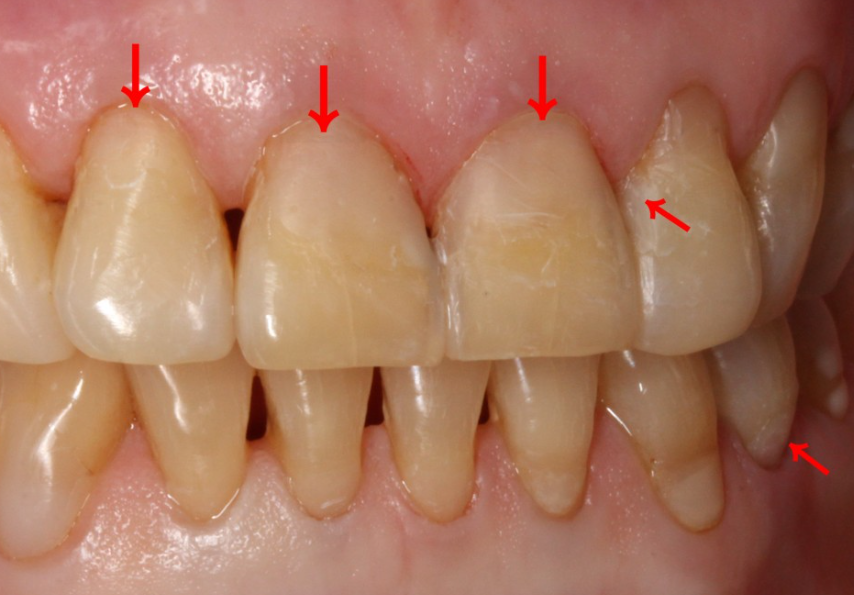

치이마모증이란?

잇몸 경계 부위의 치아 표면이 닳는 것으로

잇몸의 경계 부위가 파이거나 치아가

닳는 것을 치아마모증이라고 합니다.

앞니 치아마모증은 다른 치아보다

유독 눈에 많이 띄기 때문에

웃거나 말할 때 치아 고민으로

무삭제라미네이트 블랙필름 상담을

진행하는 경우가 많습니다.